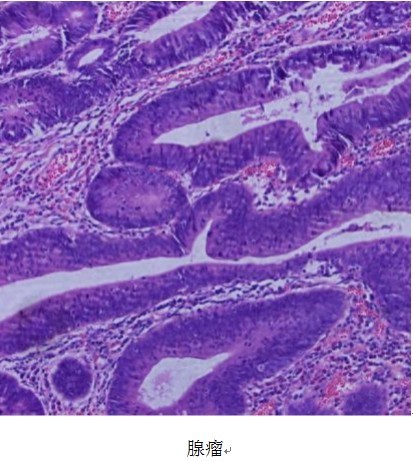

违法的程度不同,造成的后果也就不一样。还有一种息肉,里面的细胞属于严重违法。不光生长速度更快,而且还向周围的隐窝侵犯。更有甚者,有的细胞永远不再成熟,不管是底部还是顶部,永远都可以分裂。当这样违法的细胞越来越多,违法的方式足够丰富时,所谓英雄还是枭雄的出现就成为可能:这就是当前或者将来的癌细胞。如果说原先的违法者还是土匪,只知道占点小便宜,难成气候,那么癌细胞出现后则有可能发生重大变革。这些枭雄细胞还会分泌促进血管生成的物质,使息肉可以得到充足的血供。就像收保护费或收税一样,至少成了占山为王的地方武装,将来甚至可能建立政权和中央对抗。如果这些细胞不再满足于上皮细胞的层面,开始向胃肠道的平滑肌层侵犯。甚至侵透了胃肠道,侵犯到肠壁外面。少数还能顺着血流到达肝脏建立根据地,那就是不折不扣的大肠癌了。有这样潜质的息肉叫做腺瘤.。

所以,结肠息肉长的快慢,将来前途如何,和违反什么样的基因法律有关。违反的越多,就越可能长出息肉,越可能向结肠癌方向发展。目前已经知道了结肠上皮细胞变成癌细胞最常违反的几条。肥胖、高脂饮食、低运动量可以教唆上皮细胞违反法律,但如何教唆还不清楚。如果能够完全搞清其中的机制,将来就有可能通过饮食或者服药进行预防。在此之前,用结肠镜发现腺瘤,并且在结肠镜下把其摘除,是最好的预防腺瘤变成结肠癌的方法。